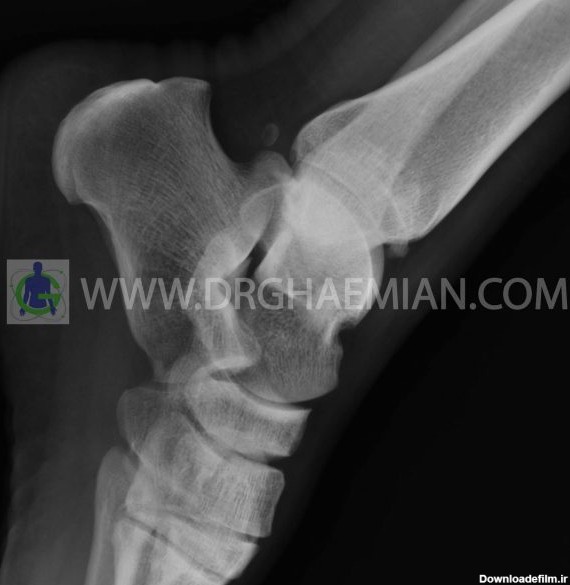

عکس از مچ پای زن

شکستگی مچ پا از جمله آسیبهای مچ پا است که در تصادفات رانندگی و ورزشکاران بیشتر دیده میشود. در این عارضه یک یا چند استخوان در مچ پا دچار شکستگی میشود و شایعترین نوع آن، شکستگی قوزک خارجی پا است که در اثر شکستگی انتهای استخوان فیبولا ایجاد میشود.